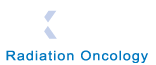

The Axellis system is used in the Treatment Center to capture 3D patient images for input to the

The Axellis Patient Imaging System can be used to accurately monitor the patient in 3D throughout

a treatment period and from session to session, enabling treatment professionals to make informed

decisions regarding the efficacy of the treatment plan and helping to minimize interruptions to

treatment regimes .

The digital data captured from the patient surface is processed and imported into the Linear

Accelerator Treatment Planning System within 2 seconds; where it can be variously used to monitor

patient movement to control ‘Gating’, provide dynamic dose calculation updates during radiation

treatment.

The system can also be used to provide guided Stereotactic Radiotherapy for the treatment of

Trigeminal Neuralgia where the system has the potential to significantly improve treatment by reducing

toxicity and improving control rates.